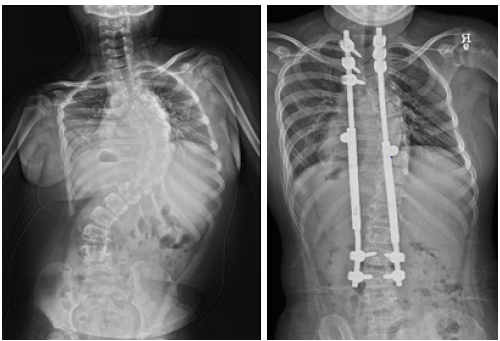

- 성장이 많이 남은 어린 아동에서 측만증이 심할 경우 그림과 같이 만곡의 위아래에만 일시적 고정 후 성장할 때 마다 강봉을 늘려 성장이 종료될 때까지 만곡의 진행을 방지합니다.

- 성장이 끝난 경우에는 교정이 필요한 모든 척추체에 고정을 하고 강봉을 이용하여 만곡을 교정하고 교정 후에는 골유합을 시행하게 됩니다.